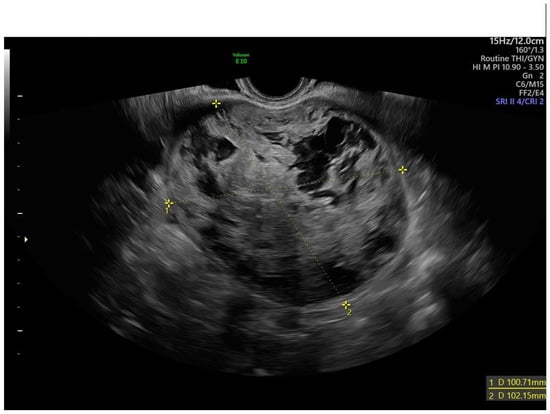

2.3. Ultrasound Assessment